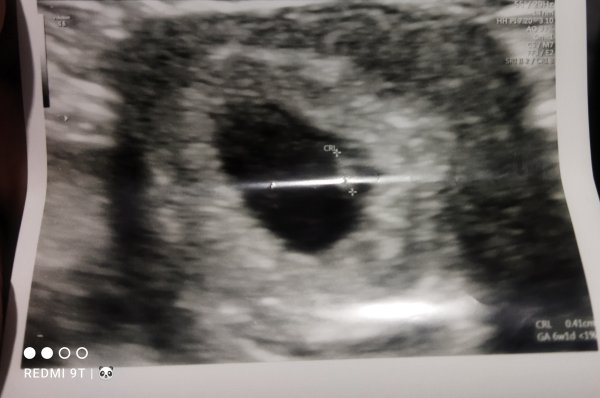

Admin inanın ne yaptım anlamadım ilk paylaştığım görüntü arkadaşımın yanlış oldu silmeyi de inanın bilmiyorum benim görüntü bu karından incelermisiniz lütfen

Hayatım tam resimde bakacağım yer parlamış bir şey göremiyorum başka resim yüklemen mümkün olur ise değerlendirmek isterim.

Suda var benim elim titriyor galiba netlestiremiyorum. Aslında şuan çok net fakat yükleme esnasında mi bulaniklasiyor anlamadım.

Ekli dosyalar

• IMG_20230217_204115.jpg

IMG_20230217_204115.jpg

24,4 KB · Görüntüleme: 148